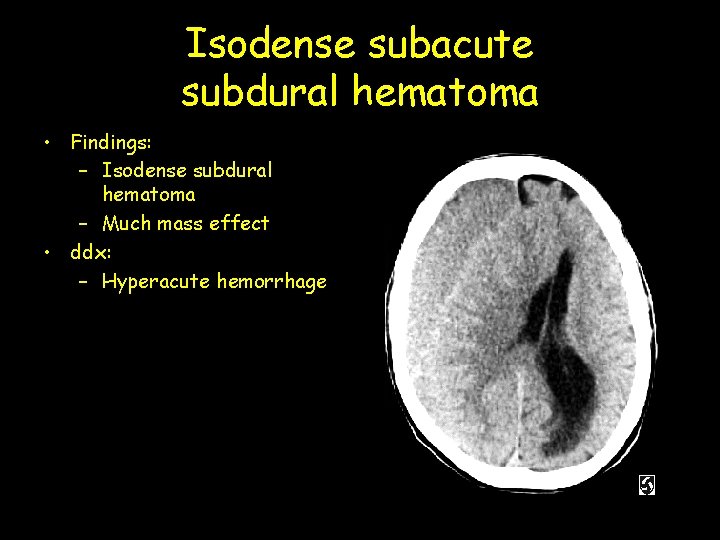

Isodense subacute subdural hematoma • Findings: – Isodense subdural hematoma – Much mass effect • ddx: – Hyperacute hemorrhage